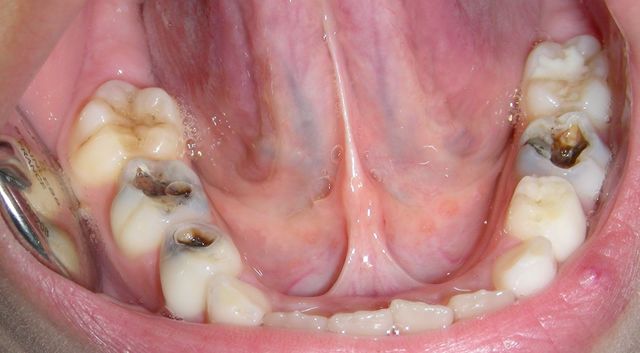

Entre los factores de riesgo que han sido relacionados con la enfermedad de la caries dental, se encuentran:

- Alto grado de infección por Estreptococos mutans.

- Alto grado de infección por lactobacilos.

- Experiencia de caries anterior.

- Eficiente resistencia del esmalte al ataque ácido.

- Deficiente capacidad de remineralización.

- Dieta cariogénica.

- Mala higiene bucal.

- Baja capacidad buffer de la saliva.

- Flujo salival escaso.

- Apiñamiento dentario moderado, severo, tratamiento ortodó